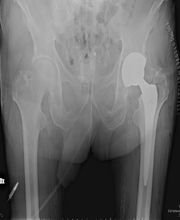

Il Dr. Grillo Pier Paolo, laureato con lode in Medicina e Chirurgia, è specializzato in Ortopedia, Traumatologia e Fisioterapia. Dal 1980 lavora presso il CTO di Torino, ove attualmente presta servizio presso la Clinica Ortopedica Traumatologica Universitaria in qualità di Dirigente Ortopedico - Traumatologo di I° Livello, che svolge la sua attività di sala operatoria, ambulatori specialistici e pronto soccorso. Si occupa prevalentemente di chirurgia del ginocchio e dell'anca con riferimento: Chirurgia protesica(totale, parziale, revisioni e reimpianti, trattamento delle complicanze settiche), Chirurgia artroscopica (ricostruzioni legamentose LCA-LCP, meniscectomie selettive, suture meniscali, trattamento dei danni cartilaginei),chirurgia della patologia rotulea (riallineamenti prossimale e distale,trattamento della lussazione recidivante,condroplastica, ricostruzione legamento patello-femorale) chirurgia delle deformità (ginocchio varo o valgo), traumatologia, patologie degenerative post-traumatiche. Ha partecipato a numerosi congressi, convegni e corsi di aggiornamento in Italia e all'estero; ha partecipato a numerosi Cadaver Lab all'estero in qualità di Tutor; è coautore di numerose pubblicazioni scientifiche edite a stampa. Per contatti e prenotazioni: studio medico: Studio Medico Crocetta - c.so Galileo Ferraris 107, Torino tel.: 011-5818892. Per ulteriori informazioni visitate il sito: www.studiocrocetta.it.